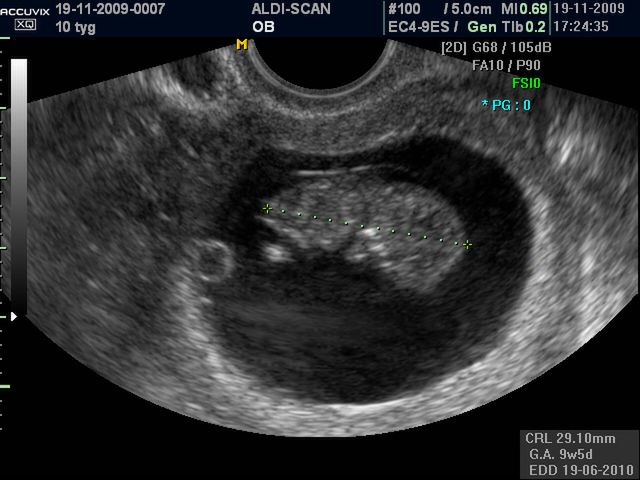

Płód w 10 tygodniu ciąży (zdjęcia)

Płód waży ok. 4 g., powstają kubki smakowe, które umozliwią dziecku rozróźnienie smaków